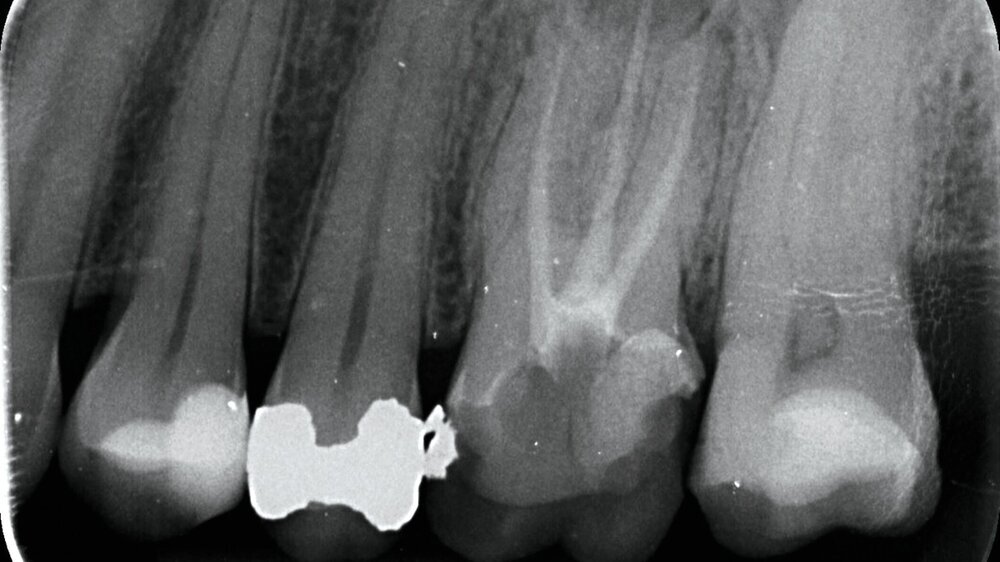

Im Februar 2022 stellte sich die 46-jährige Patientin nach Überweisung durch die Hauszahnärztin mit seit zwei Wochen bestehenden Schmerzen im linken Oberkiefer in einer MKG-chirurgischen Praxis vor. Klinisch und radiologisch zeigten sich eine tiefe Karies an Zahn 26 mit apikaler Ostitis und enger Beziehung zur Kieferhöhle (Abbildung 1) sowie der devitale Zahn 27.